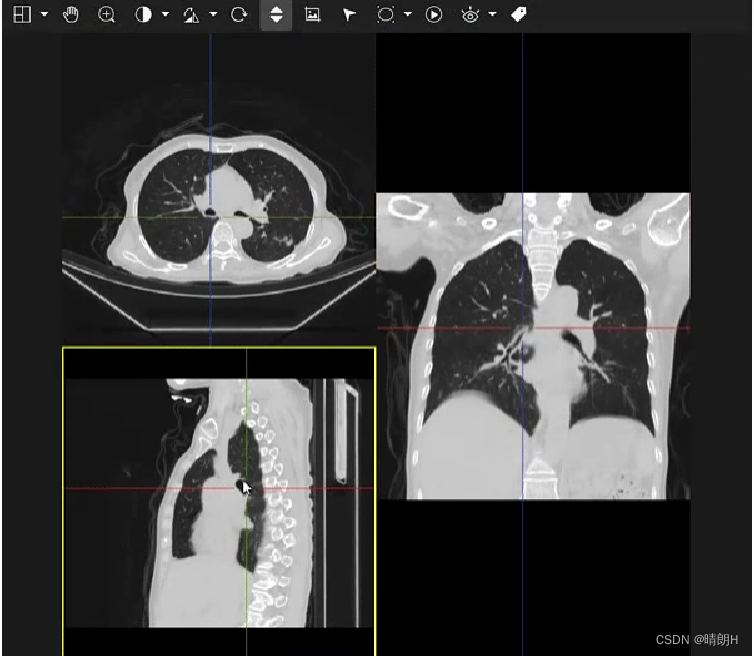

现在还没有结束,在DICOM中,你可以将身体水平、垂直或斜向切断,如下面所示。